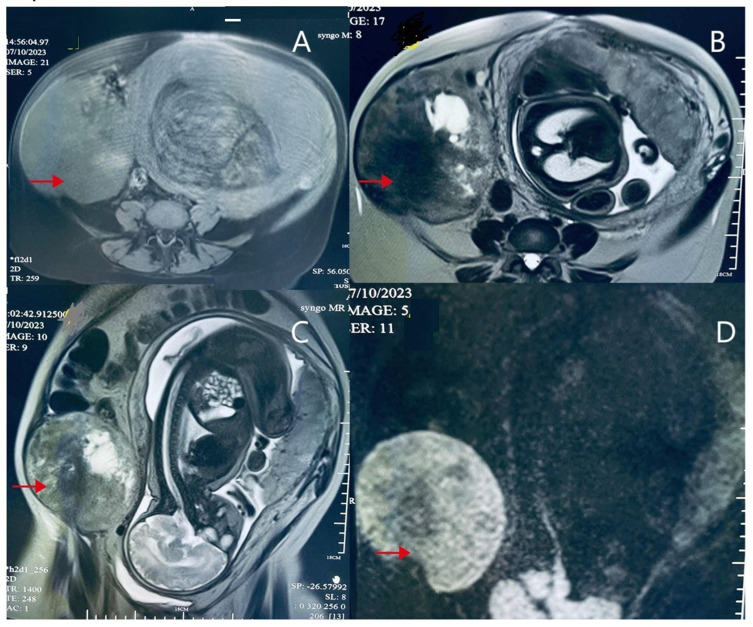

目的:关于妊娠相关的结缔组织增生纤维瘤(DF)的数据不多,主动监测作为主要治疗策略的有效性仍不确定。因此,我们的病例说明DF肿瘤可以持续到妊娠晚期。终止妊娠结合手术切除肿瘤可以减少创伤和并发症,最终产生一个健康的婴儿。病例介绍:本病例描述了一位怀疑患有硬纤维瘤瘤的孕妇,她拒绝终止妊娠,选择密切监测直到妊娠晚期,并成功分娩了一个健康的婴儿。结论:本病例揭示了个体化、多学科管理方法的可行性和潜在安全性,如主动监测和及时手术干预。它强调了平衡母体和胎儿风险的重要性,并提出了可能有助于在涉及妊娠相关DF的类似复杂情况下的临床决策过程的见解。

Case presentation: This case describes a pregnant woman with a suspected desmoid fibromatosis tumor who refused termination of pregnancy, opting for close monitoring until late gestation and successfully delivering a healthy baby.